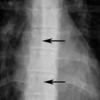

Anterior junction line